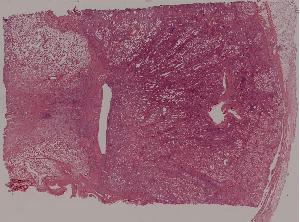

71. Acute transplant rejection of kidney